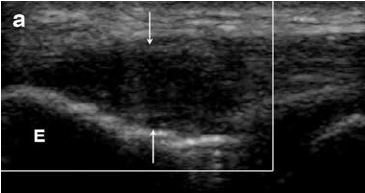

초음파 검사상

힘줄이 어두워지고,

지저분해지고

퉁퉁 부어 두꺼워집니다.

팔꿈치 외측 힘줄이 어두워지고, 지저분해지고, 부어있습니다.

초음파상 관절낭이 부어있습니다.